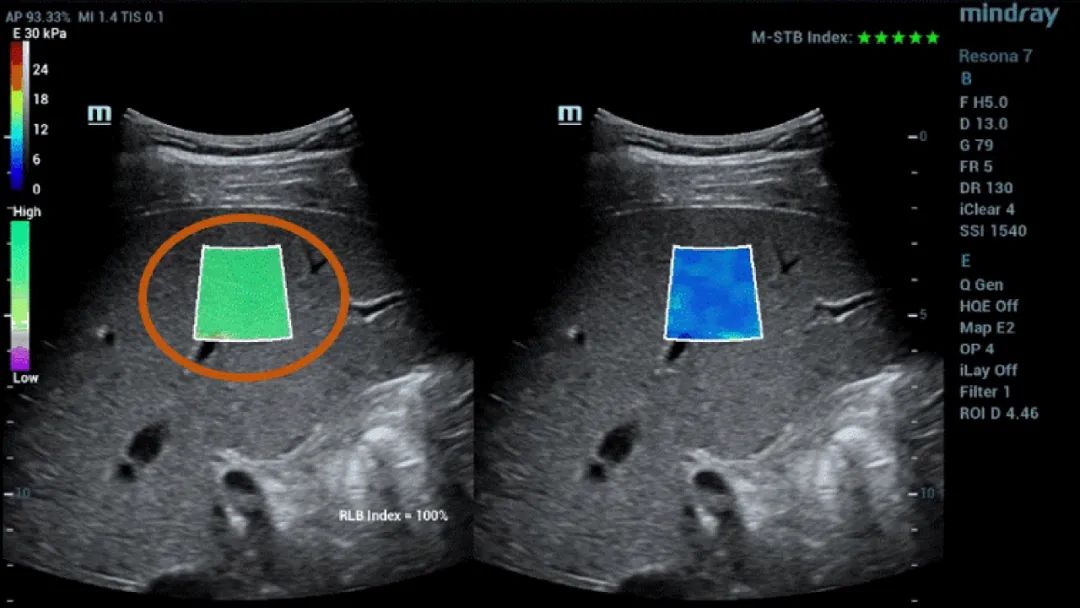

Figure 1 (continuación): (e) Imágenes obtenidas con SWE 2D (STE; Mindray, Shenzhen, China). Se proporcionan dos criterios de calidad: el índice de estabilidad de movimiento (M-STB), que se indica con estrellas (la estabilidad más alta se muestra con cinco estrellas verdes), y el esquema de confiabilidad (RLB), que va de violeta a verde, siendo este último el que indica la confiabilidad más alta. Las estrellas son indicadores de movimiento durante la adquisición. Si hay menos de cuatro estrellas, significa que hay un movimiento considerable durante la adquisición y ese cuadro no se debe usar para la medición de la rigidez hepática.(f) Imágenes obtenidas

Además, la elastografía Sound Touch (STE) de Mindray ofrece potentes factores de calidad o confianza, incluido el índice de estabilidad de movimiento (M-STB), el mapa de confiabilidad (RLB), el índice de confiabilidad (RLB), etc., para las mediciones obtenidas con elastografía de ondas transversales 2D, lo que ayuda a los operadores a confirmar los estándares de adquisición de imágenes.

El índice de M-STB indica la estabilidad del movimiento del tejido producida por la respiración del paciente o la compresión del operador, que ayuda a eliminar la interferencia del movimiento. Se indica mediante estrellas (la estabilidad más alta se muestra con cinco estrellas verdes), una imagen confiable debe tener ≧4 estrellas verdes.

El mapa de RLB indica la confiabilidad de las imágenes de STE, que va de violeta a verde, siendo este último el que indica la confiabilidad más alta. Si el índice de RLB es ≧90 %, la imagen es confiable.